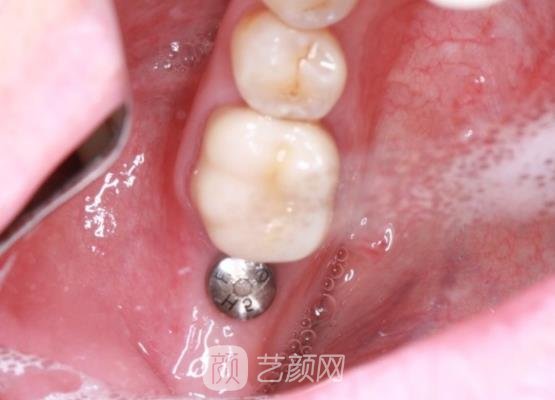

两个多月左右过去了,拔牙之后留下的牙槽洞愈合好了,到医院进行了种植。和医生沟通之后选择了合适的种植系统,医生先会对口腔内部进行检查,确定没有一些口腔疾病和伤口,接着便是放入种植体,操作的手法也是比较精巧的。因为之前注射了麻醉,也很顺利。

大概过去了三个多月,伤口基本上已经愈合好了。医生打电话通知我到医院进行二期安装,到医院进行检查之后,牙槽骨已经愈合好了,在上边安装了基台和牙冠。医生的手法一直是很不错的,态度也很好,安装好之后有一些异物感存在,不过这个是能够接受的。